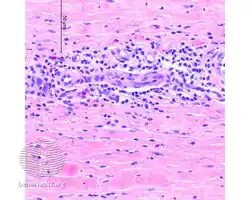

Additional images

-

Eosinophilic fasciitis/pathology -

Eosinophilic fasciitis/pathology